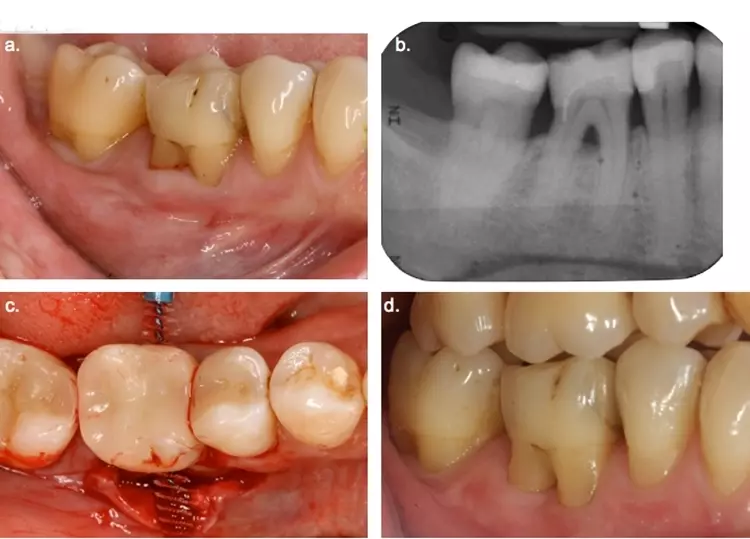

Auch im 1. Quadranten bestanden erhöhte residuale Sondierungstiefen. Zunächst wurde die Situation mit einer DVT-Aufnahme radiologisch dargestellt und das genaue Vorgehen geplant.

Entsprechend den ermittelten Befunden und insbesondere dem zirkulären Restattachment der bukkalen Wurzeln des Zahnes 16 wurden die Entfernung lediglich der palatinalen Wurzel sowie eine distale Keilexzision an Zahn 17 geplant [2]. Vor der Operation wurde der Zahn 16 wurzelkanalbehandelt und mit Komposit provisorisch versorgt. Nach marginaler Schnittführung, Degranulierung und Defektdarstellung konnte die palatinale Wurzel entfernt werden.

Dr. Mauro Amato & Prof. Clemens Walter